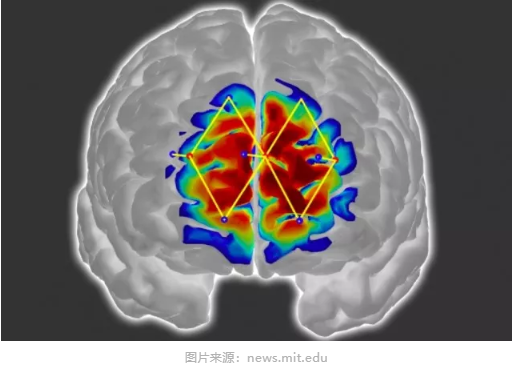

研究团队描述了一种量化患者疼痛的方法,他们利用功能性近红外光谱技术(fNIRS)这种新兴的非侵入式脑功能成像技术,检测患者氧合血红蛋白浓度,从而揭示其神经元活动。概括来说,研究人员将fNIRS传感器置于受试者前额来测量其前额皮质活动,通常前额皮质在疼痛处理中起重要作用。利用测量到的大脑信号,研究人员进而开发个性化的机器学习(Machine Learning)算法来检测与疼痛反应相关的含氧血红蛋白水平的模式。该模型能够以87%的准确率检测出患者是否有疼痛情况。

fNIRS传感器被置于患者前额,不同波长的近红外光穿过头骨进入大脑。含氧血红蛋白和脱氧血红蛋白吸收波长不同,它们的信号略有变化。当红外信号回传到传感器时,信号处理技术便会计算每种血红蛋白在大脑不同区域的含量。当患者感受到疼痛时,大脑中与疼痛相关的区域会出现含氧血红蛋白增多、脱氧血红蛋白减少的情况,这些变化都可以通过fNIRS检测到。